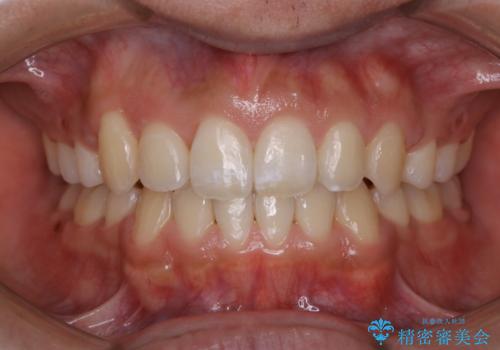

オーディションで歯並びを指摘された:自信をもって歌える口元へ

気になる前歯を治したい 短期間でのインビザライン矯正

上下前歯のデコボコをきれいに インビザラインによる矯正治療